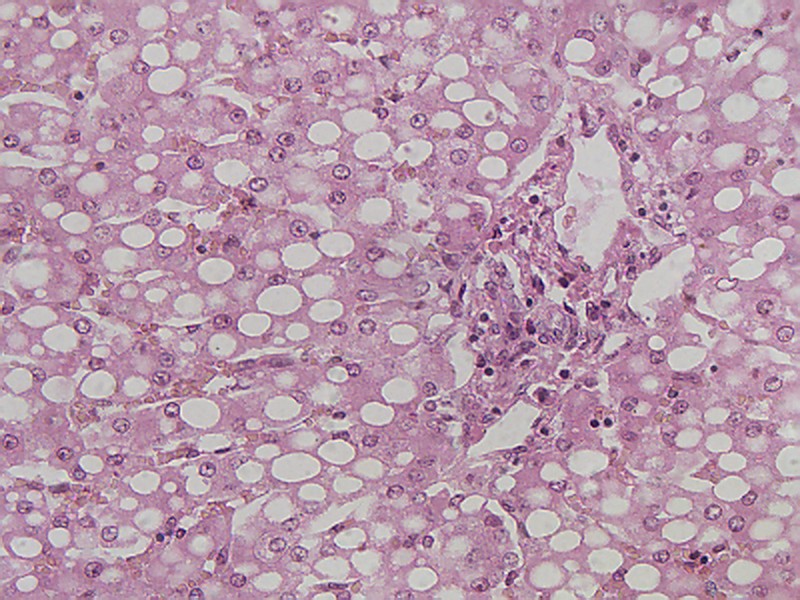

染色:HE染色                  放大倍数:400X

肝脏切片